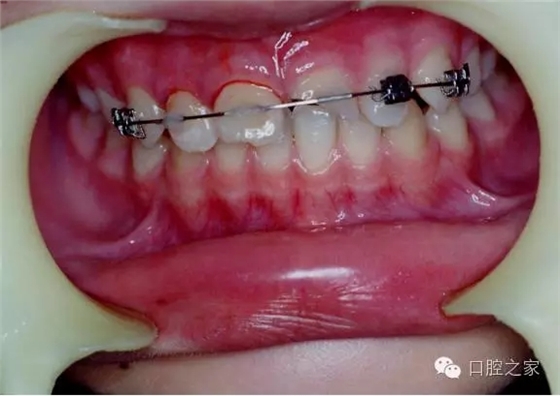

五、托槽輔助固定法